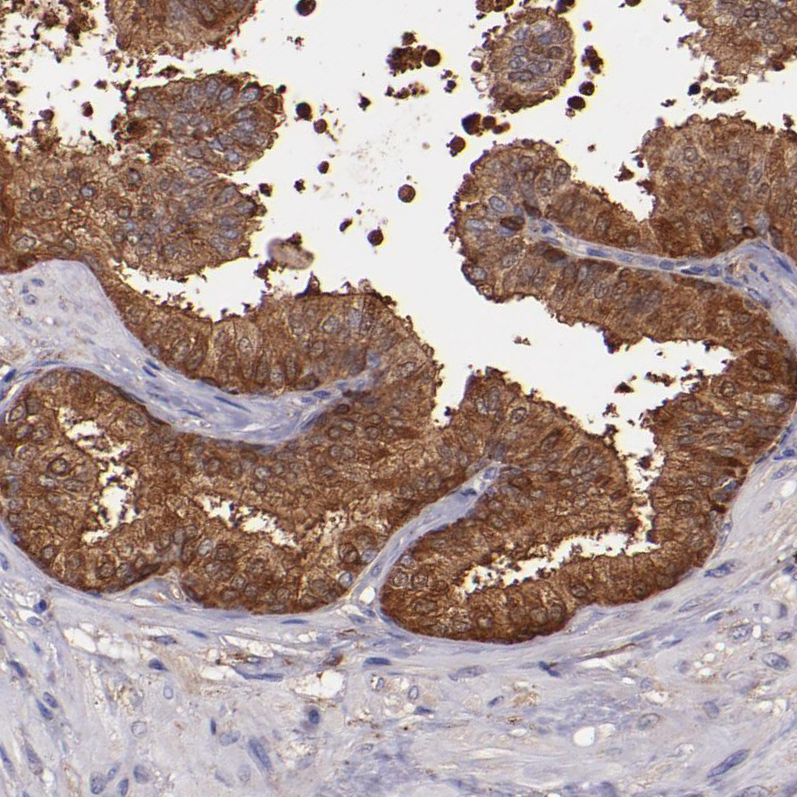

Immunohistochemical staining of human prostate shows strong cytoplasmic positivity in glandular cells.